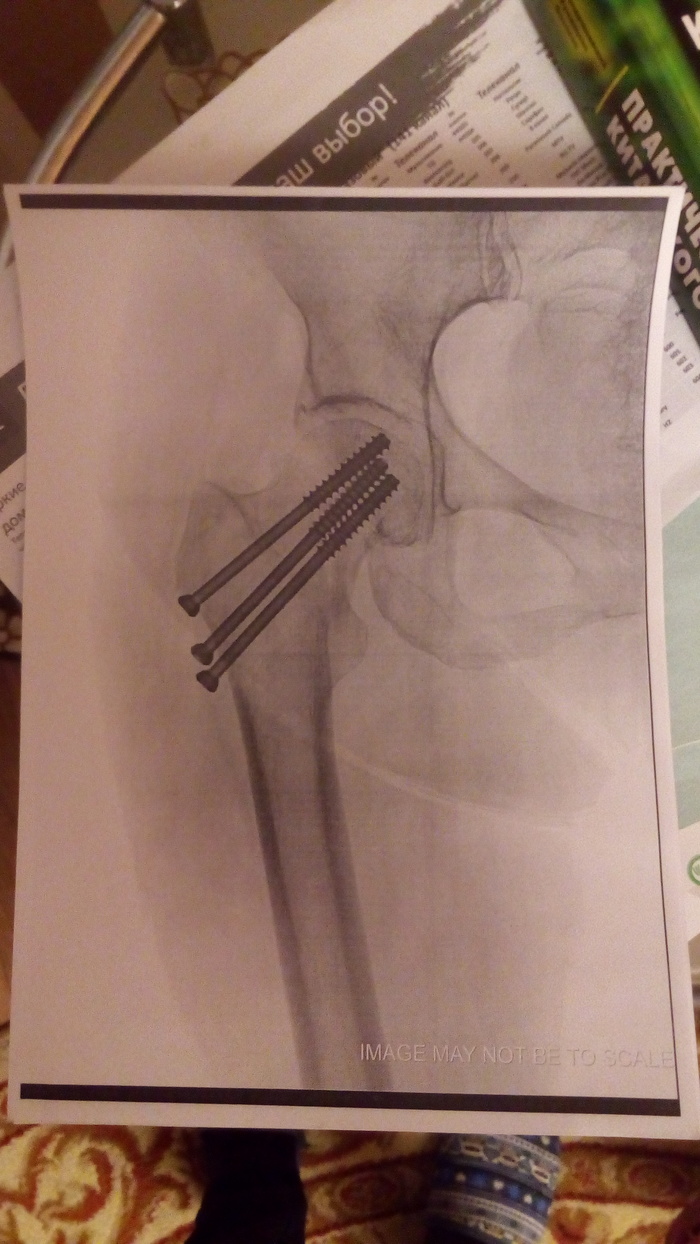

Восьмого декабря этого (2019-го) года. Мама в маршрутке упала и с сломала шейку бедра. Водитель дождался скорую. По приезду поставили обезбаливающее. Я это к чему всё? Если у Ангелов есть крылья, они синего цвета - те, кто везут до больницы, и коричневые те, кто делает экстренные операции. Как вы можете видеть, "собрали" сразу. В этот же час. Я приехал, маму уже везли на операцию. Так вот. Снимки - выше. Вы творите Чудеса.